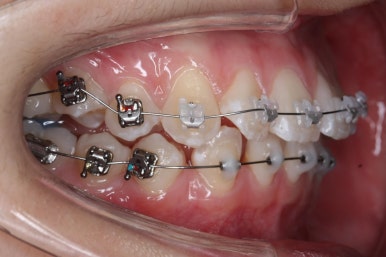

가지런하게 하는 작업을 계속 합니다.

또한 왼쪽 위 작은 어금니 하나를 추가로 발치했습니다. 치아 갯수를 맞출 목적 + 우측으로 쏠린 앞니의 중앙을 개선하기 위함 입니다.

이제 어느 정도 치열이 가지런해졌습니다. 앞으로 해야 될 단계는 앞니 틈을 줄이고, 이 뽑은 자리 틈을 줄이면서 중앙선을 개선하고 아래쪽 어금니를 앞으로 당겨오면서 교합을 맞추며 앞니 갯수를 맞춰줍니다.

부산교정 키다리아저씨치과에서는 이번에 마이크로 임플란트라는 장치를 추가로 사용하였습니다.

잇몸뼈에 교정 치료기간동안 잠깐 사용하는 매우 작은 스크류인데요. 단단히 고정시켜 놓고, 어금니를 당겨오는데 사용합니다.

틈을 줄여주고, 어금니를 당겨오고 중앙선을 맞춰줍니다.